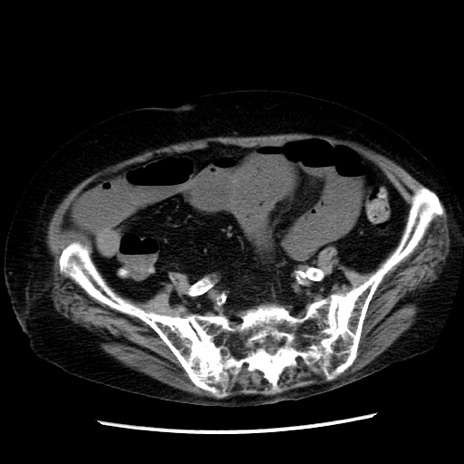

症例14(横断像)

【症例】 90歳代女性

【主訴】 腹痛・嘔吐

【現病歴】今朝から左側腹部痛を認めた。 経過観察していたが、嘔吐を認めたため来院。

【既往歴】 子宮癌術後

【身体所見】 意識清明、BP 127/54mmHg、P 98bpm Sp02 95%(RA)、BT 35.8°C、腹部平坦・軟腸ぜん動音聴取良好、右下腹部圧痛(+) 反跳痛なし

【データ】WBC 9800、CRP 0.46